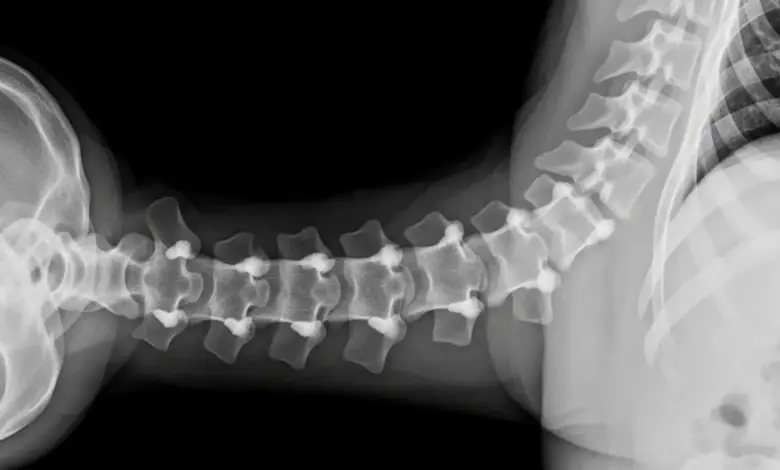

A artropatia facetária é uma das causas mais comuns de dor na coluna.

O problema começa nas facetas — as pequenas articulações que ligam uma vértebra à outra. Quando sofrem desgaste ou inflamação, tarefas simples ficam travadas: virar o pescoço, levantar da cadeira, amarrar o sapato.

A artropatia facetária ocorre quando as facetas sofrem desgaste, inflamação ou sobrecarga mecânica. A cartilagem perde qualidade, o líquido sinovial pode reduzir e as superfícies passam a gerar atrito.

O resultado é dor, rigidez e limitação de movimento, com piora ao estender a coluna ou ficar muito tempo em pé.

As facetas ficam na parte posterior da coluna e trabalham em dupla com os discos intervertebrais. Juntas, estabilizam e permitem flexão, extensão, inclinação e rotação.

- Radiografia para avaliar alinhamento e sinais de artrose.